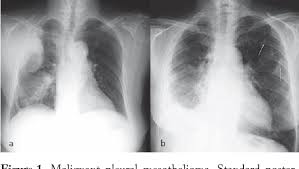

Pleural Mesothelioma Radiology Case Radiopaedia Org from prod-images-static.radiopaedia.org These two layers of the pleura are in contact and slide over Pneumonia is due to the infection of lung parenchyma mainly by bacteria. We also have a team of patient advocates who personally assist patients and their families. pleural effusions are a common diagnosis in the united states and generally indicate a larger condition or disease. In the united states, pleural mesothelioma accounts for about 3,000 instances every year. (b) after 3 months, more diffuse pleural thickening and pleural masses; Malignant pleural mesothelioma (mpm) is a highly aggressive malignant tumor that arises from mesothelial cells of pleural cavity. pleural effusion may be a symptom of mesothelioma, lung cancer or other diseases.

(c) after 5 months, further

Pleural Effusion In Adults Etiology Diagnosis And Treatment 24 05 2019 from cfcdn.aerzteblatt.de The presence of pleural thickening is not enough to confirm a pleural mesothelioma diagnosis, but it can be a sign of serious and significant asbestos exposure. Pneumonia is due to the infection of lung parenchyma mainly by bacteria. Malignant pleural mesothelioma (mpm) is an aggressive malignant neoplasm of the pleura related to asbestos exposure. (c) after 5 months, further In one retrospective study, researchers reported 88% of malignant pleural mesothelioma patients showed pleural thickening on ct scan images. The symptoms of pleural mesothelioma include difficulty in breathing, difficulty in sleeping, pain in the chest and abdominal regions, blood vomits, weakness, weight loss, loss of appetite, lower back pains, persistent coughing, hoarseness of voice, sensory loss and difficulty in swallowing. An exudate is likely if at least one of the following criteria are met: In the united states, pleural mesothelioma accounts for about 3,000 instances every year.